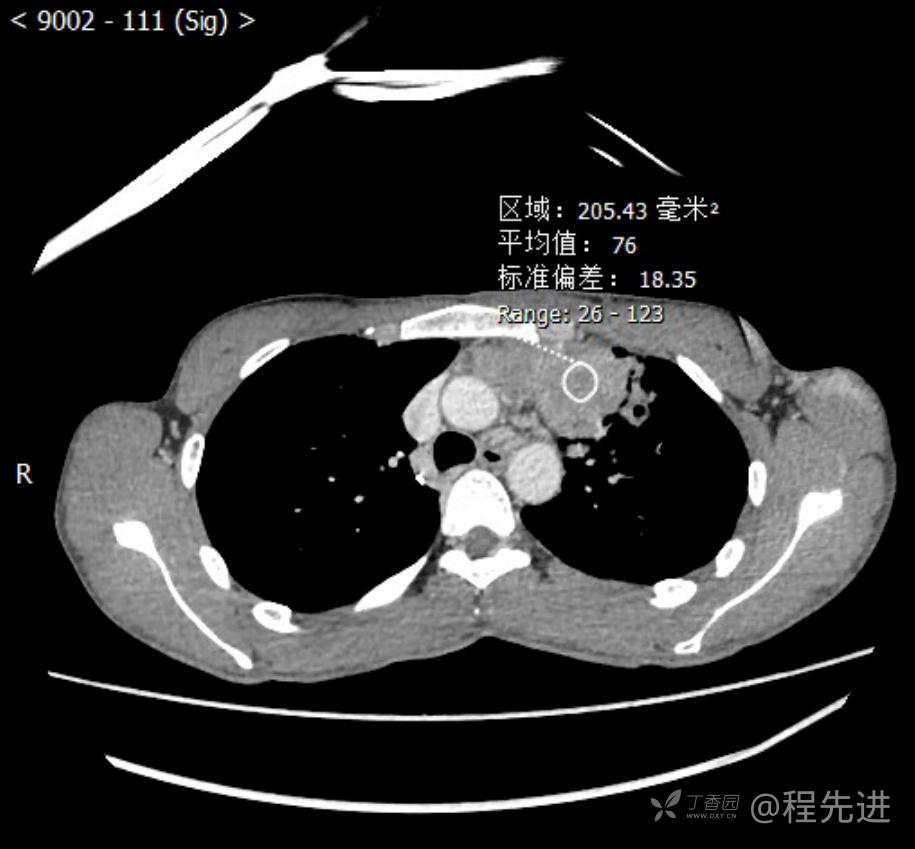

主诉:反复咳嗽1月,发现“纵隔”占位半月,乏力10余天。

现病史:患者1月前无明显诱因出现咳嗽,以夜间为著,伴有少量白痰,无发热,无胸痛、咯血,无痰中带血,未予重视,半月前外院行胸部CT检查发现“左前上纵隔”占位,未予进一步检查及治疗。近10余天自觉乏力,逐渐加重。